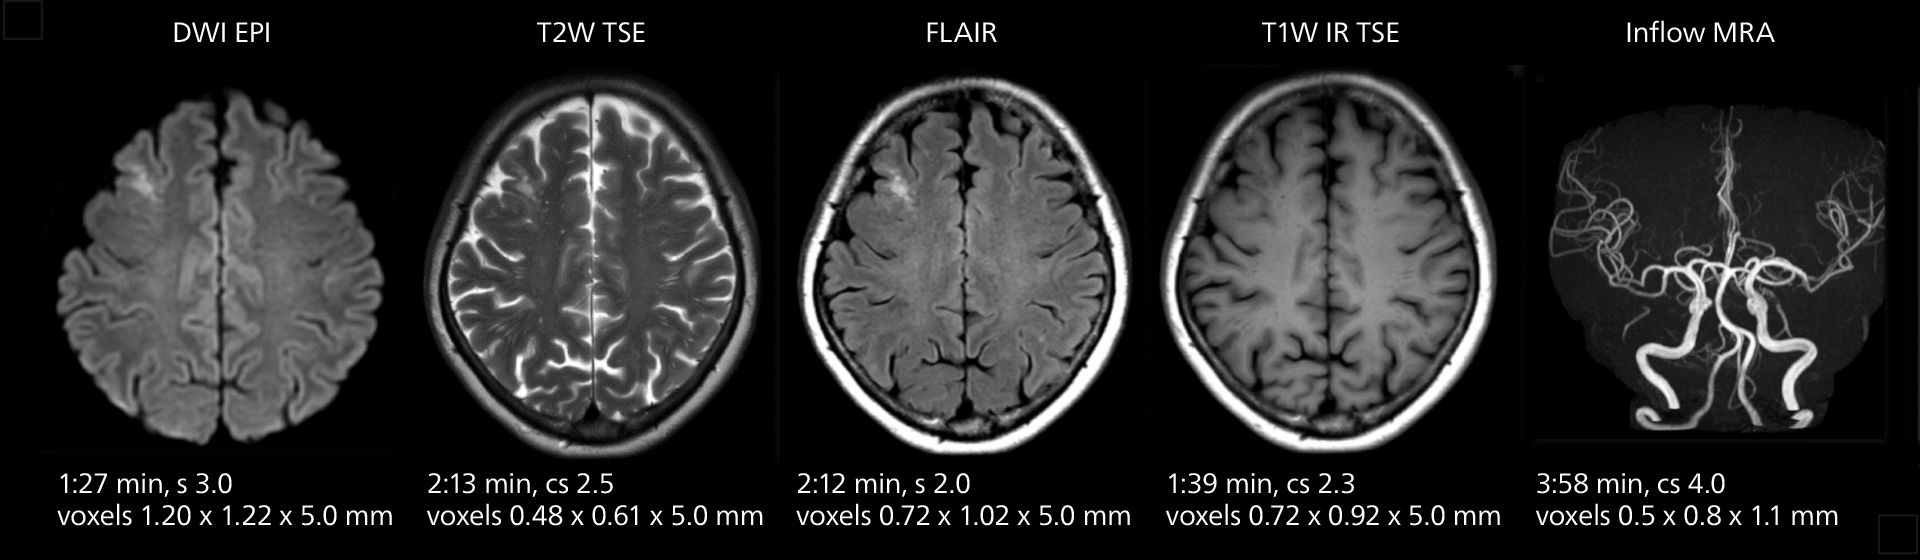

Brain MRI

These images of an old cerebral infarction demonstrate the speed and image quality after upgrading to Elition X.

Brain MRI

These images of an old cerebral infarction demonstrate the speed and image quality after upgrading to Elition X.